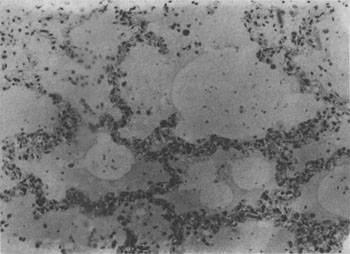

发生水肿的组织,体积增大,颜色苍白,镜下可见水肿液积于细胞和纤维结缔组织之间或腔隙内。由于水肿液含血浆蛋白,故HE染成粉红色。肺水肿时,肺泡腔内充满水肿液(图3-16)。切开肺时可有泡沫状液体自切面溢出。脑水肿时脑回变扁平,脑沟变浅。镜下,脑灰质和白质疏松,血管周围间隙加宽。严重时脑组织在高倍镜下呈网化状态。严重脑水肿时可形成脑疝。

图3-16 肺水肿

肺泡腔内有水肿液及漏出的红细胞,肺泡壁毛细血管扩张充血